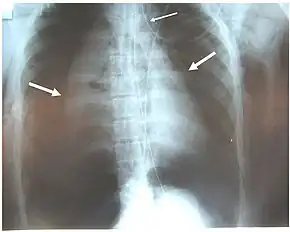

a)Collapsed right lung , left deviated trachea , and shifted heart b) chest illustrating collapsed right lung and shifted heart

Chest x-ray is the initial imaging technique used to diagnose TBI.[17] The film may not have any signs in an otherwise asymptomatic patient.[15] Indications of TBI seen on radiographs include deformity in the trachea or a defect in the tracheal wall.[17] Radiography may also show cervical emphysema, air in the tissues of the neck.[2] X-rays may also show accompanying injuries and signs such as fractures and subcutaneous emphysema.[2] If subcutaneous emphysema occurs and the hyoid bone appears in an X-ray to be sitting unusually high in the throat, it may be an indication that the trachea has been severed.[4] TBI is also suspected if an endotracheal tube appears in an X-ray to be out of place, or if its cuff appears to be more full than normal or to protrude through a tear in the airway.[17] If a bronchus is torn all the way around, the lung may collapse outward toward the chest wall (rather than inward, as it usually does in pneumothorax) because it loses the attachment to the bronchus which normally holds it toward the center.[6] In a person lying face-up, the lung collapses toward the diaphragm and the back.[23] This sign, described in 1969, is called fallen lung sign and is pathognomonic of TBI (that is, it is diagnostic for TBI because it does not occur in other conditions); however it occurs only rarely.[6] In as many as one in five cases, people with blunt trauma and TBI have no signs of the injury on chest X-ray.[23] CT scanning detects over 90% of TBI resulting from blunt trauma,[3] but neither X-ray nor CT are a replacement for bronchoscopy.[6]